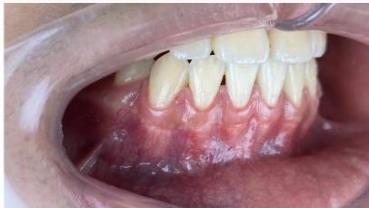

### b) Intraoral Examination

Intraoral examination revealed severe proclination and protrusion of both the maxillary and mandibular incisors [6]. The occlusal relationship was Class I at the canine (tooth 3) and first molar (tooth 6) levels bilaterally. A critical unfavorable biological factor was the proximity of the mandibular incisor roots to the labial cortical plate, representing a high-risk condition when planning extraction-based anterior retraction mechanics [10-12]. All four third molars were present.

Figure 2: Pre-Treatment Intraoral Photographs